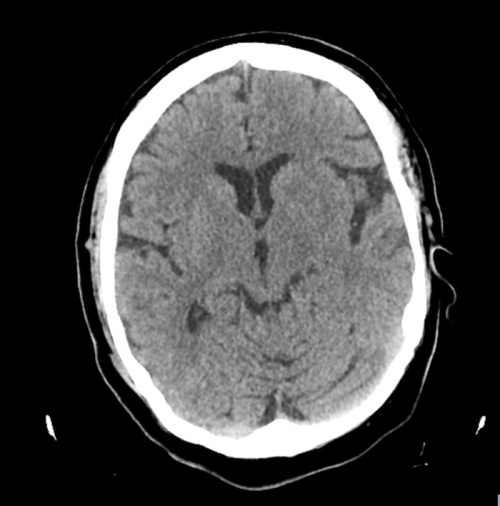

WebLa tomografía computarizada (TAC) cerebral es una prueba diagnóstica rápida: que suele durar menos de 1 minuto o hasta 5 minutos cuando se usa contraste. Si el TAC.

WebPor lo general, la prueba dura unos 20 minutos, en los que solo se debe estar tumbado en una camilla dentro de un tubo que genera rayos X. Puede que el TAC dure un poco más. WebEl TAC de cráneo es efectivo para diagnóstico de tumores cerebrales. Cuando se aplica contraste , de algunos de ellos se definen mejor sus características o se detecta mejor..

WebSi la prueba se realizará en áreas cerebrales, tomará un tiempo de 20 a 30 minutos. Es importante considerar que, a esa cantidad de tiempo, se le deben sumar los 60 minutos. Web¿Cuánto tiempo dura un TAC cervical? El examen tarda de 10 a 15 minutos.. Posiblemente necesite contener la respiración por períodos de tiempo breves. El movimiento puede. WebUna TC de la cabeza es un tipo de exploración que utiliza rayos X para crear imágenes detalladas de la cabeza, incluyendo el cráneo, el tejido cerebral y los vasos.